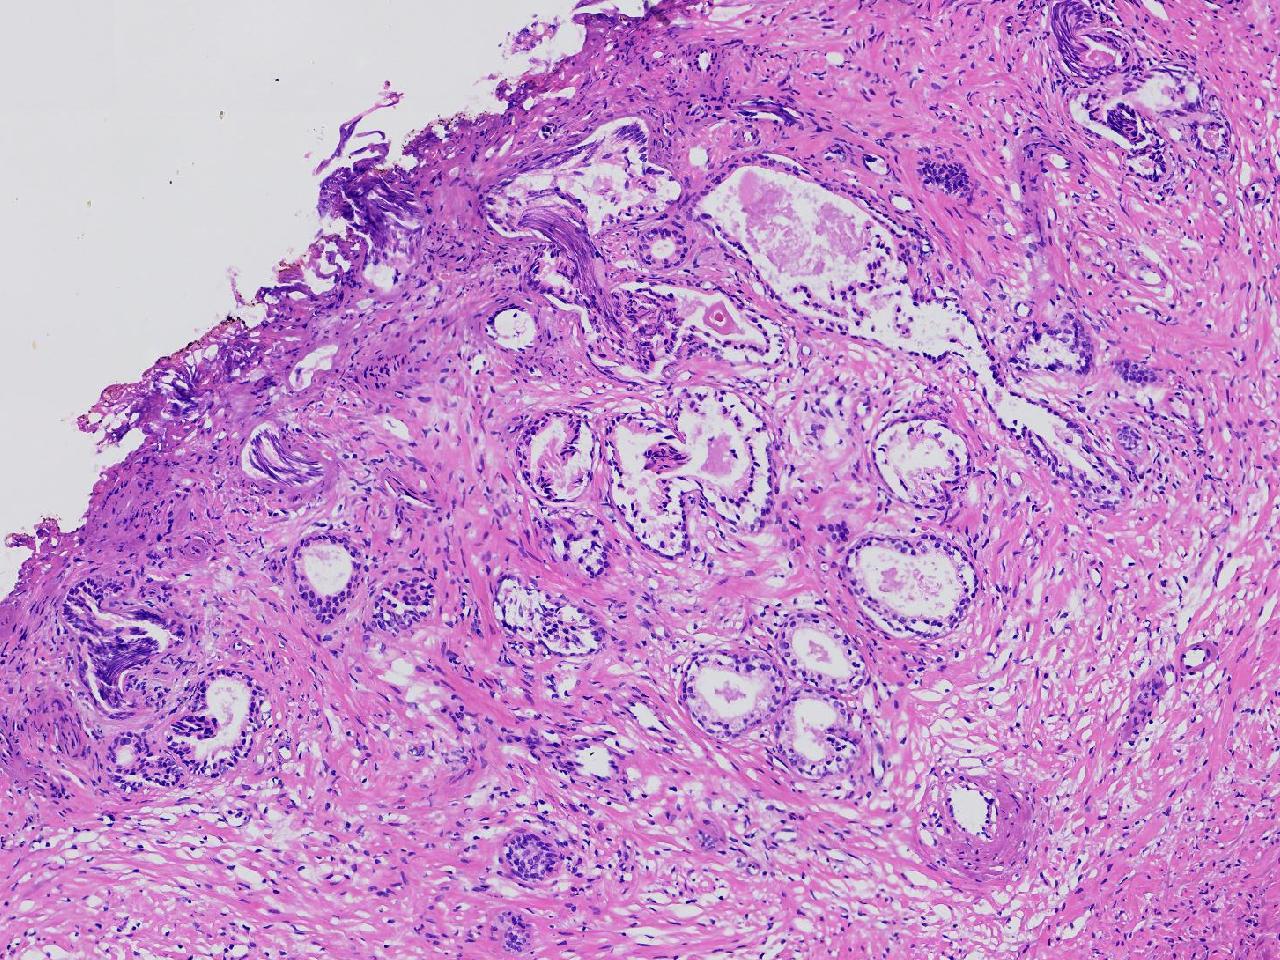

良性前列腺增生?

男,68岁,排尿困难半年余。行前列腺前切术。

前列腺电切标本

灰粉色条索状软组织多块,4X3X3厘米。

考虑为良性前列腺增生症

良性增生

BPH.